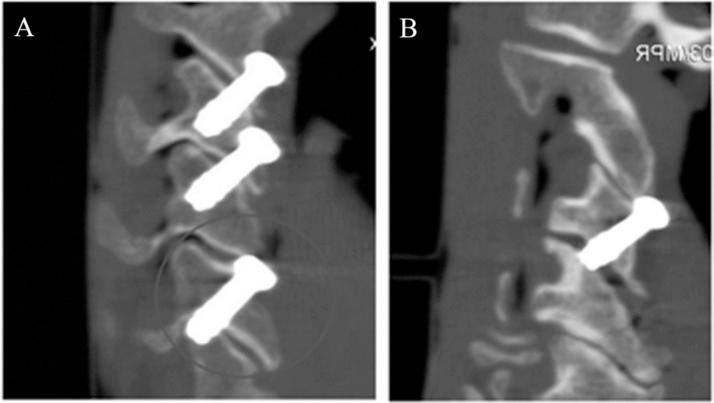

结果

共置入48枚螺钉。45枚螺钉的置入是可接受的。3例螺钉位置不当的情况包括1例关节突骨折、1例关节突分离,以及在1例C7上关节突较小的标本中1枚C6 - 7螺钉接触C7神经根。

结论

我们的数据表明,采用适当的影像学技术和瞄准导向器,在靶向阶段无需侧位透视荧光镜检查即可安全地在C3 - 7置入经皮经关节突螺钉。然而,由于C7侧块形态测量的变异性,在C6 - 7置入经关节突螺钉时必须小心。